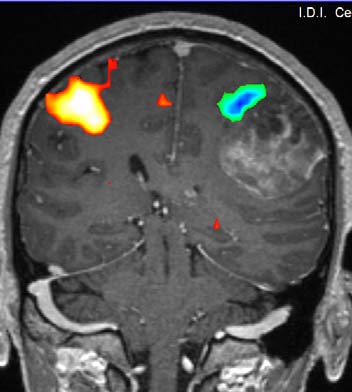

La exploración de RM en neurorradiología puede utilizar algunas técnicas especiales como son la espectroscopia, difusión, perfusión, angiografía, la tractografía y RM funcional que permiten obtener información metabólica, de movimiento molecular microscópico, de la hemodinámica cerebral, de las arterias y venas, de la estructura de las fibras cerebrales y de la actividad cerebral. Estas técnicas se emplean para el estudio de enfermedades vasculares, tumores, procesos neurodegenerativos y de forma previa a la cirugía cerebral para evitar lesionar zonas importantes del cerebro.

Resonancia Magnética cerebral funcional.

Se muestra en color las áreas del cerebro que se activan cuando se mueven las manos.